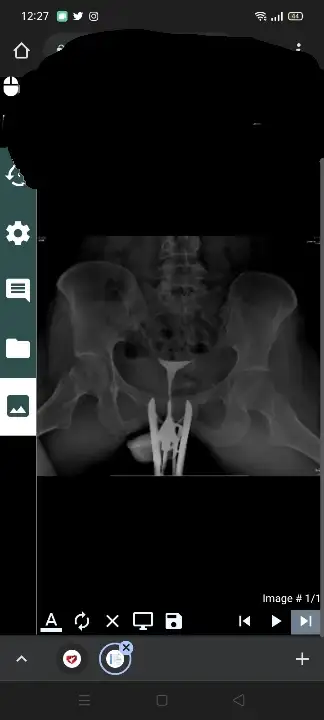

Merhaba arkadaşlar ben geçen ramazan ayında hsg çektirdim de cektirdigim doktor hafif tıkanıklık vardı açıldı dedi ama en son gittiğim doktorum da sanki açılmamış gibi dedi hiç kafasına yatmamış Bir iki ay deneyelim olmazsa tekrar çekeceğim dedi ama ben hiç çektirmek istemiyorum tekrar size gostersem anlarmisiniz

Kuzu raporda normal yazıyor herşey. Bende de öyle oldu. Solda akış az dediler kateter ile girip açtılar. Tazdikli sıvı vererek açılıyormuş. Doktor baktı açmışlar dedi.. sonra sanki sıvı varmış gibi çekmişler belki açtıklarına dair sıvılı olan kısmıda bilerek çekmişler dedi. Sonomed olduğu için doğru işlem yapılmış dedi.

Bence sen raporunu başka doktora da göster. HSG rötgen gibi görüntüyü doktorlar aşinalar zaten iyi bir doktor yorum yapar. Sadece raporu okuyorsa o kadar anlamıyordur. başka doktor bul..

Buda görüntüler

Ya bilmiyorum işte biri açıldı dedi biride açılmamış gibi dedi artık hangisi doğru hangisi yanlış bende çözemedim

Burda bunlardan kimse anlamaz ki 🤷‍♀️

Doktorlarda raporu çok önemsemiyor, görüntülere bakarak yorum yapıyor

Seninde raporunda temiz gözüküyor, sıkıntı yok gibi ama doktorun belki görüntülerde kafasına yatmayan bi durum vardır kuzu